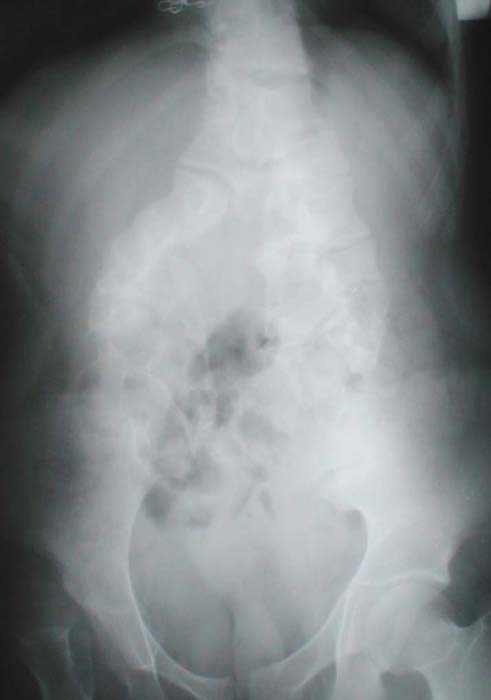

Женщина, 17 лет. Диагноз: тяжелая аномалия развития поясничного отдела позвоночника и таза, спинномозговая грыжа пояснично-крестцовой области с моноплегией в правой ноге, обострение хронического внутреннего геморроя.ЭПИКРИЗПри поступлении жалобы на отсутствие активных движений и чувствительности в правой ноге, наличие опухолевидного образования в пояснично-крестцовой области.Со слов девочки, нарушение движений и чувствительности в правой ноге наблюдается с самого рождения. Живет и учится в условиях Новотроитской школы-интерната. В 1997 г. Имел место перелом н/з правого бедра.Общее состояние удовлетворительное. Сознание ясное, поведение адекватное. В пояснично-крестцовой области пальпируется мягкотканое образование размерами ?20х15х5см, с кожей не спаяно. В неврологическом статусе менингеальных знаков нет. Со стороны черепных нервов легкая асимметрия носогубных складок. Вялая плегия в правой ноге с выраженной мышечной атрофией, укорочение ноги до 15 см. S-образное искривление правой ноги в коленном и голеностопном суставах. Показывает анальгезию с уровня Л1-Л2 сегментов справа с полным нарушением мышечно-суставного чувства в правой ноге. Сухожильные рефлексы с рук и левой ноги живые, с правой ноги не вызываются. Функция тазовых органов произвольная.На рентгенограммах от 14.01.03г. отмечается аномалия развития пояснично-крестцового отдела позвоночника: асимметричное расщепление позвоночника, рахишиз. Вертлужная впадина правого тазобедренного сустава атрофирована и скошена, головка бедренной кости вне вертлужной впадины - гипоплазия вертлужной впадины, осложнившаяся подвздошным вывихом бедренной кости с вальгусной деформацией в коленном суставе и варусной в голеностопном суставе, гипертрофией капсулы - фиброзный анкилоз.МРТ-исследование 13.010.3г. - определяется аномалия развития поясничного отдела позвоночника и костей таза: полное расщепление тел поясничных позвонков, отсутствие дужек, гипоплазия боковых масс крестца, отсутствие тел крестцовых позвонков, расширение и полное расщепление дурального мешка. Гипотрофия мышц таза справа.Исследование в лаборатории биомеханики.Реовазография нижних конечностей. Пульсовое кровенаполнение на уровне бедра справа (паретичное) усилено в 5 раз, на голени тонус сосудов справа снижен в 2 раза. Качественно снижен венозный отток.Хронаксиметрия. Возбудимость и проводимость нервно-мышечного аппарата ног снижена по малоберцовым нервам с 2х сторон : справа на 22 %, слева на 18%.В связи с наличием незначительных кровянистых выделений из прямой кишки осмотрена хирургом - обострение хронического внутреннего геморроя, получила курс лечения гемостатиков.16.01.03г. произведена ректороманоскопия: патологических изменений не выявлено.16.01.03г. осмотрена гинекологом: генитальный инфантилизм (?) Показано УЗИ гениталий. УЗИ гениталий 16.01.03г.: патологии не выявлено.